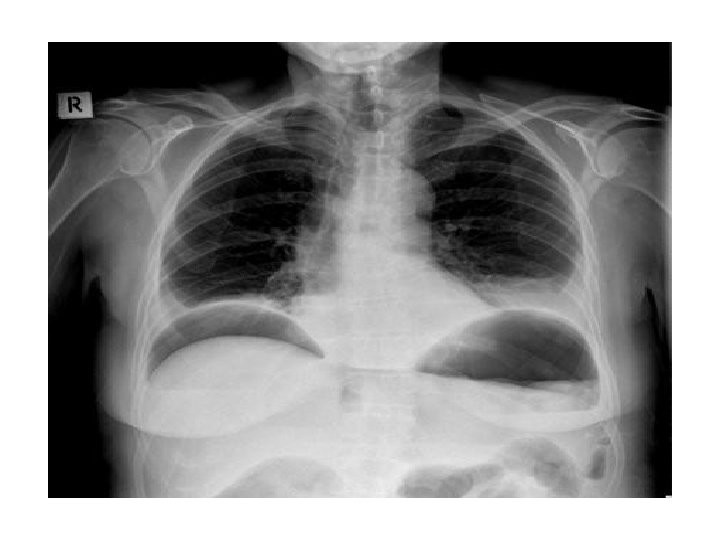

Pleural Effusion • • • Obliteration of the costophrenic angle Obliteration of the cardiophrenic angle Tracheal deviation Meniscus sign Compensatory hyperinflation Causes : heart failure, nephrotic syndrome, cirrhosis, pneumonia, tuberculosis, mesothelioma, bronchogenic CA, SLE, trauma.